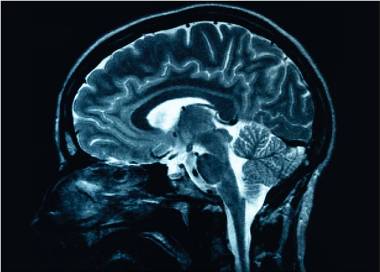

Oamenii de ştiinţă au constatat că îmbătrânirea cerebrală este mai accelerată la bărbaţi decât la femei. Într-un recent studiu, cercetătorii explică de ce bărbaţii pierd mai rapid volum cerebral odată cu vârsta, indiferent dacă au sau nu Alzheimer, transmite News.ro.

Noul studiu, publicat recent în revista Proceedings of the National Academy of Sciences – PNAS, arată că, deşi femeile sunt diagnosticate mai des cu boala Alzheimer, creierul bărbaţilor suferă o reducere mai rapidă a volumului odată cu înaintarea în vârstă. Această constatare oferă o nouă perspectivă asupra modului în care diferenţele biologice dintre sexe pot influenţa procesul de îmbătrânire cerebrală.

Studiul a analizat peste 12.000 de imagini RMN ale creierului provenite de la aproape 5.000 de persoane cu vârste între 17 şi 95 de ani. Cercetătorii au descoperit că, pe măsură ce îmbătrânesc, bărbaţii pierd volum cerebral mai rapid şi în mai multe regiuni decât femeile. Zonele afectate au fost în special cele responsabile de memorie, emoţii şi procesarea senzorială.

În schimb, la femei s-a observat o uşoară expansiune a ventriculilor cerebrali – spaţiile umplute cu lichid aflate în interiorul creierului – ceea ce sugerează o evoluţie diferită a îmbătrânirii cerebrale.